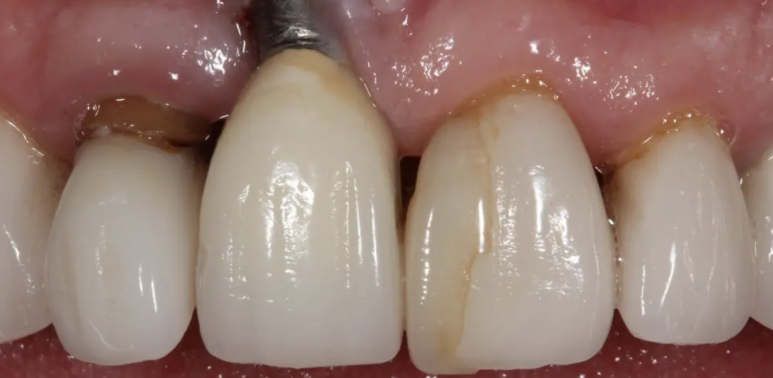

수술 직후 당일 사진 및 엑스레이

수술 직후의 사진인데요, 위 환자분의 경우 플랩리스 방식, 비절개 방식으로 발치를 하고, 임플란트 나사를 심은 후, 주변에 뼈이식을 한 후에, 임플란트에 임시치아를 직접 연결하여 제작하고, 잇몸 높이가 최대한 대칭이 맞게 끔 임시치아 모양을 조정했답니다. 플랩리스 방식으로 봉합을 하지 않고 수술을 마무리했답니다.

한번 수술에, 제가 원하는 모든 것을 한 셈이지요.